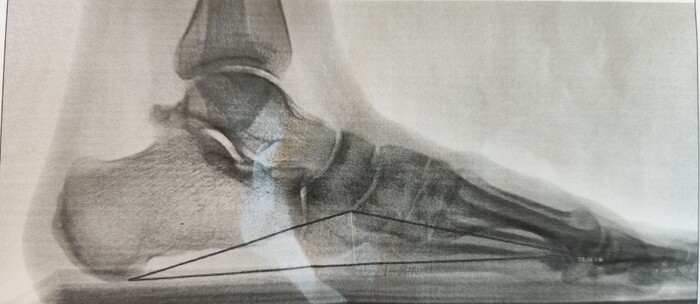

На Р-грамме левой стопы с нагрузкой: в структуре пяточной кости отмечается зона просветления костной ткани размером 29х27х17мм (точные размеры по данным КТ, которая была пройдена призывником),неправильной овоидной формы, с склеротическим контуром, соответствует кисте левой пяточной кости.

По заднему контуру таранной кости визуализируется добавочная кость- os trigonum размером 1.1х1.5см,наиболее вероятно вызывающая импиджмент-синдром заднего отдела голеностопного сустава.

Угол продольного свода левой стопы 160 град., высота 19 мм, соответствует продольному плоскостопию 3 ст. левой стопы.